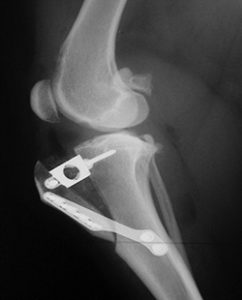

Tibial tuberosity advancement (TTA)

Tibial tuberosity advancement (TTA) requires a linear cut along the front of the shin bone. The front of the tibia, called the “tibial tuberosity” is advanced forward until the attachment of the quadriceps is oriented approximately 90 degrees to the tibial plateau (notice that this is simply another way to accomplish the same orientation as the TPLO). Again, this orientation renders the knee stable, independent of the CCL. Similar to the TPLO, the cut in the bone is stabilized by the use of a specifically designed bridging bone plate and screws. The decision between TPLO and TTA is based upon concurrent problems, surgeon preference, etc. The anatomic configuration of some dog’s knees does not lend them to safe or effective application of this technique.